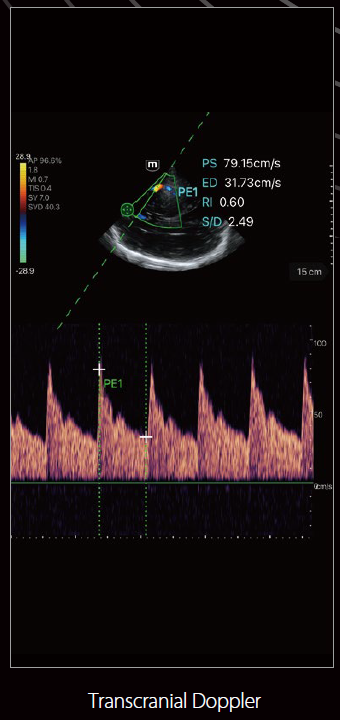

صور متعلقة